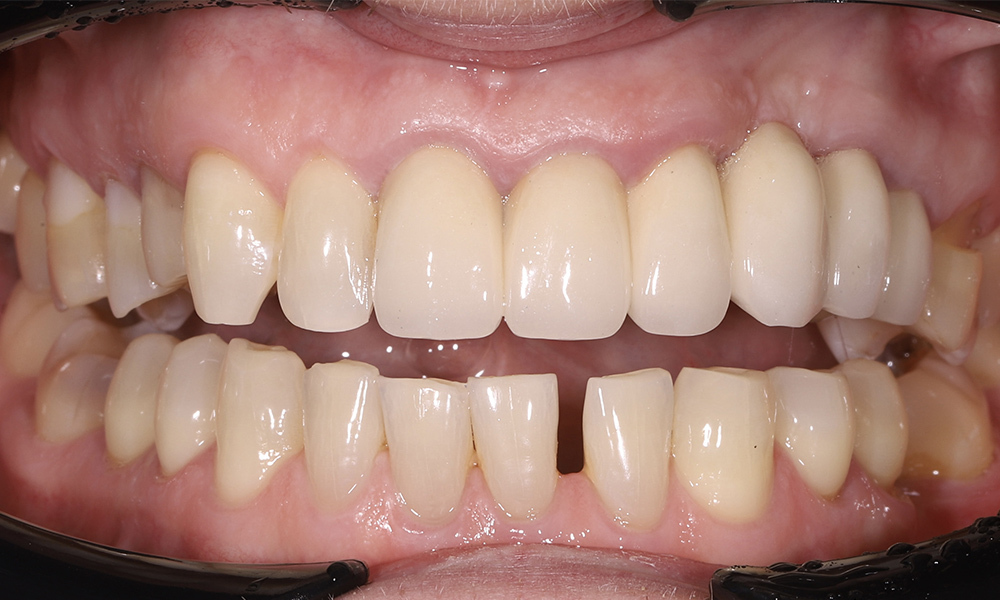

Исправление неправильного прикуса и замена устаревших реставраций для гармоничной улыбки